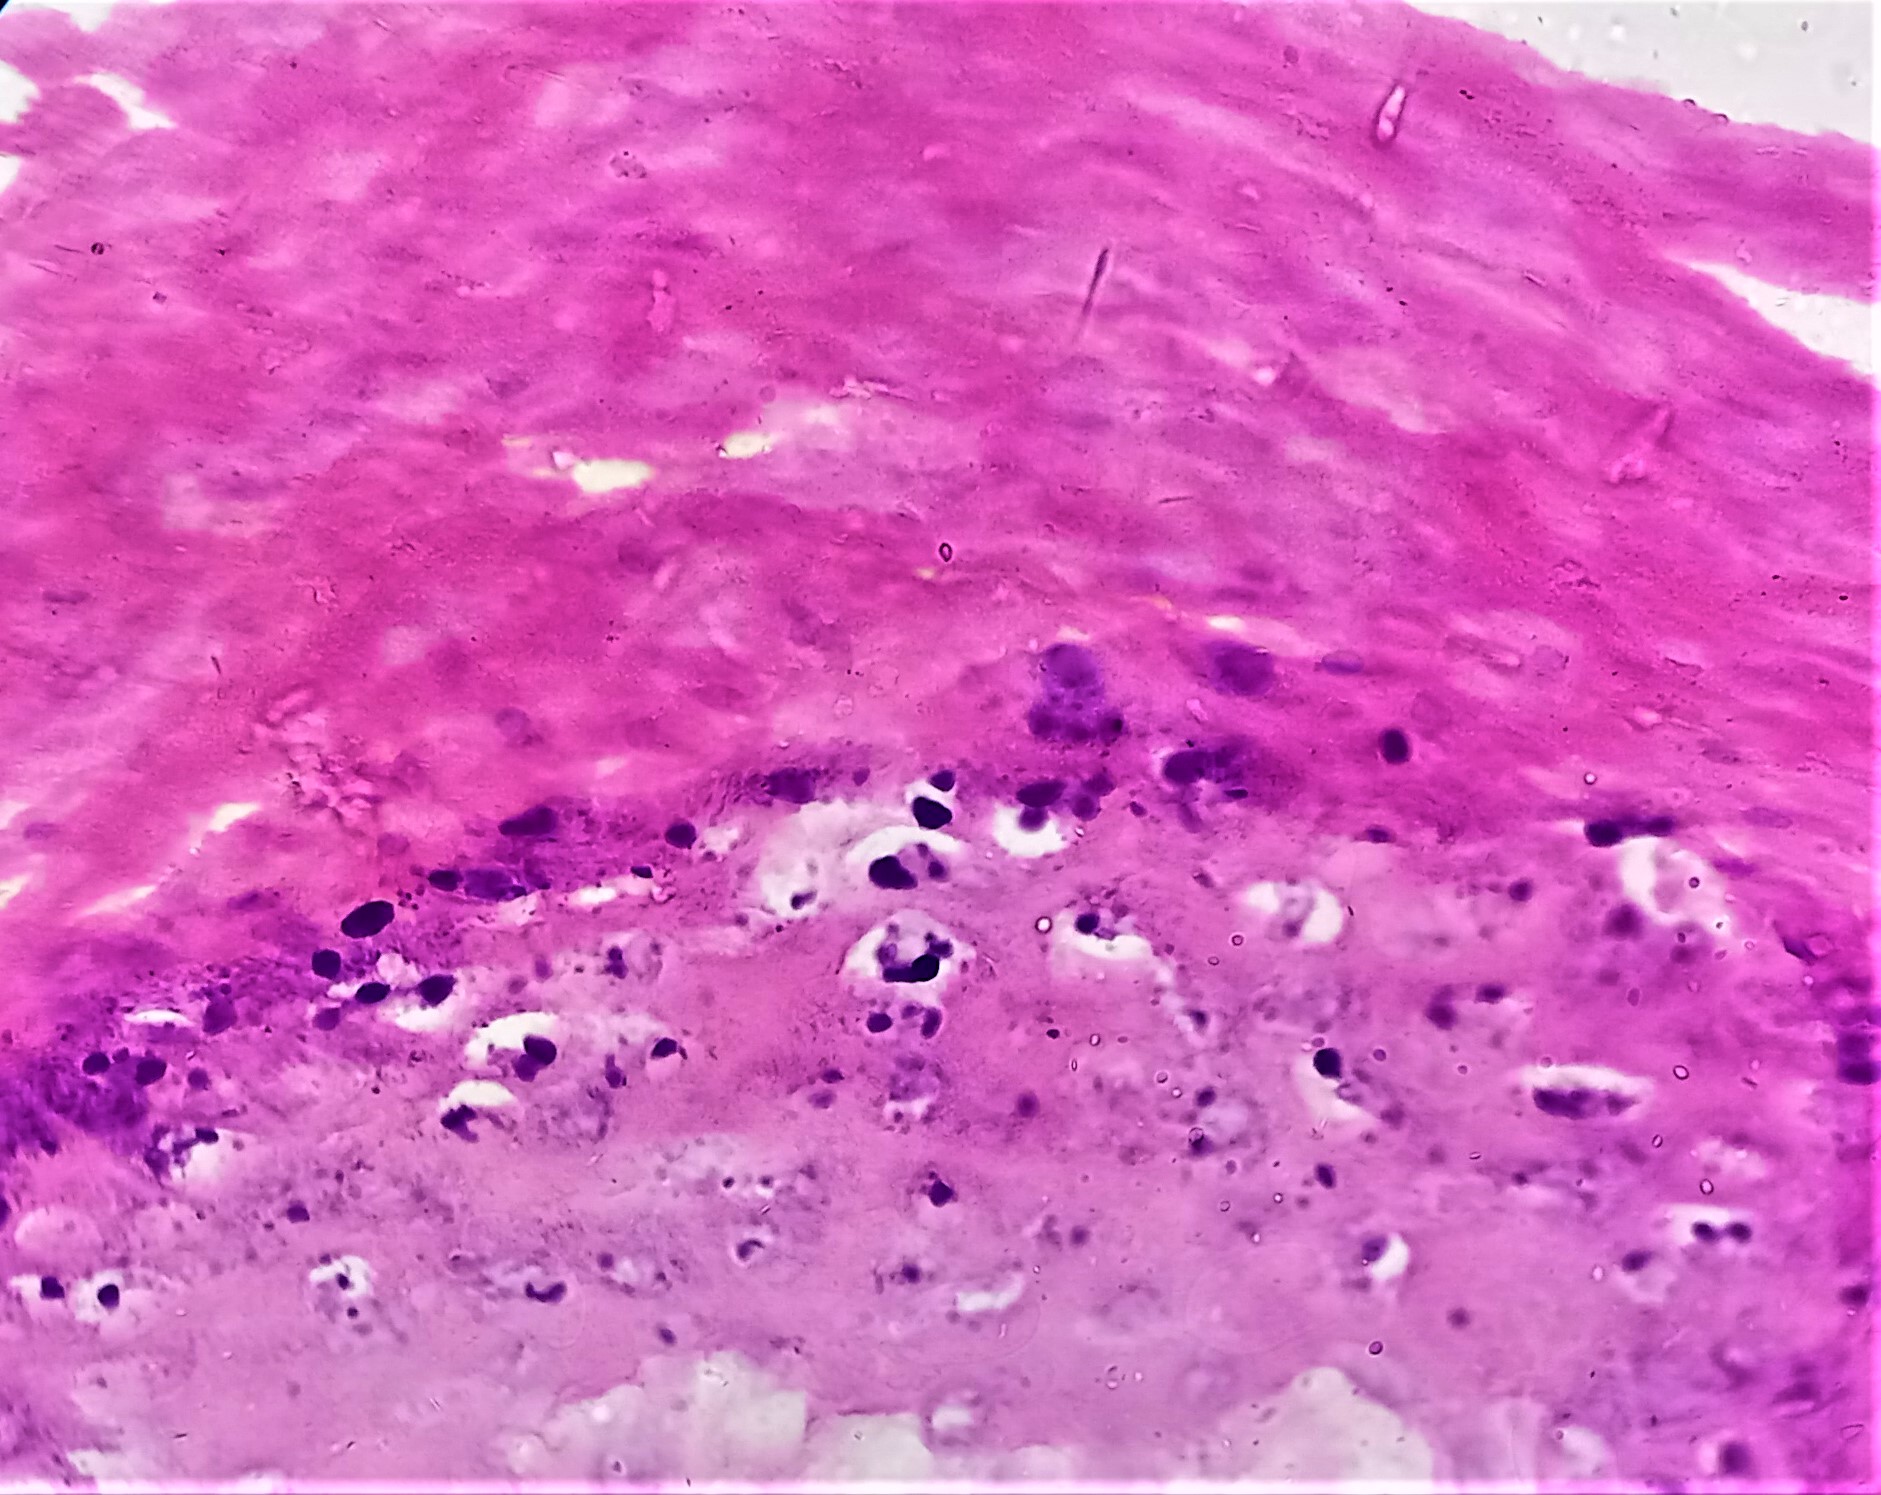

Microscopic (histologic) description

- Common warts (verruca vulgaris) (Arch Pathol Lab Med 2018;142:700):

- Hyperkeratosis, papillomatosis, hypergranulosis

- Columns of parakeratosis, especially over projecting dermal papillae

- Intracorneal hemorrhage

- Vacuolated superficial keratinocytes with pyknotic raisin-like nuclei (koilocytes)

- Koilocytes may not be seen in older lesions

- Koilocytes are not needed for the diagnosis

- Inward bending of rete ridges at borders of lesion (toeing in)

- Dilated capillaries in dermal papillae

- Projects above the plane of the epidermis

- Palmar / plantar warts (verruca palmaris and verruca plantaris) (Arch Pathol Lab Med 2018;142:700):

- Similar to verruca vulgaris (clinical distinction based on location)

- Endophytic growth - greater proportion of the lesion lies beneath the plane of the epidermis

- Myrmecia warts (J Cutan Pathol 2012;39:936):

- Marked acanthosis

- Large eosinophilic intracytoplasmic inclusion bodies

Microscopic (histologic) images

Contributed by Heba Ahmed Abdelkader, M.D., Hillary Rose Elwood, M.D., AFIP,

@MirunaPopescu13 on Twitter and @shilpa_rakesh_path on Instagram